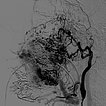

Laterale Ansicht einer digitalen Subtraktionsangiographie nach Injektion in die linke Arteria carotis externa. Die AVM ist als diffuser, netzartiger Nidus mit direktem, starken venösen Abstrom zentral in der linken Wange erkennbar (Fast-flow-Malformation).

Laterale Ansicht, DSA nach Anspritzen der linken Arteria carotis interna. Auch aus der Arteria carotis interna erfolgt eine massive Versorgung des Nidus der AVM, vor allem über die Arteria ophthalmica und den Truncus meningohypophysealis.

Dies erschwert die Embolisationstherapie erheblich.

DSA, anterior-posteriore Ansicht, nach Anspritzen der rechten A. carotis communis. Auch aus der kontralateralen rechten A. carotis externa und A. facialis rechts wird der Nidus der AVM an der linken Wange gespeist.